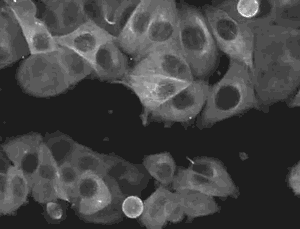

大量的临床前和临床试验表明,干细胞治疗可以加速伤口愈合,为各种难以愈合的慢性伤口的治疗带来了希望。

另一种修复是干细胞修复,这种伤害的修复是透过干细胞聚集、增生及分化后的再生机制产生的新生组织及功能,与原组织完全相同。

运用干细胞疤痕治疗是将从我们自己的脂肪或血液中提取的干细胞移植到疤痕部位的手术,移植的干细胞在我们身体中担当了细胞再生的功能。干细胞会分泌出具有提高皮肤再生作用的生长因子, 疤痕部位的皮肤会再生出来,形成胶原蛋白,疤痕会长出新的组织。

上海本正干细胞技术有限公司提供的干细胞是从脐带、胎盘中提取的一种修复器官机理的未完全分化的原始细胞,具有自我更新、多项分化和高度繁殖的能力,医学上称为“万能细胞”,它是形成人体各种组织器官的起源细胞。干细胞对临床上一些疑难疾病的治疗如:脑瘫、老年痴呆、脑萎缩、帕金森病、中风、肝硬化、糖尿病、红斑狼疮、股骨头坏死、软骨和关节损伤、心脏和脊髓损伤等,取得显著效果,它拥有更加鲜活细胞能量,可以快速、有效进入体内,分泌多种有益细胞因子,调节体内微环境,激活干细胞再生能力,重启时光之门,追溯青春绽放源头,实现对人体衰老状态减缓,同时有效改善身体亚健康以及预防肿瘤发生。